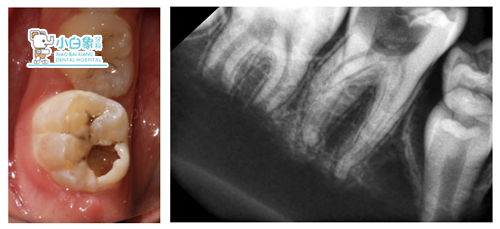

颌面部未见异常,口内查:46合面龋坏达髓角,探诊疼痛,检查温度测试疼痛。

X片:46低密度影达髓腔

诊断:46慢性牙髓炎